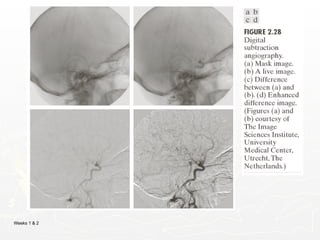

An Example of Image Subtraction: Mask Mode

Mask h(x,y): an X-ray image of a region of a patient’s body

Live images f(x,y): X-ray images captured at TV rates after injection

of the contrast medium

Enhanced detail g(x,y)

g(x,y) = f(x,y) - h(x,y)

The procedure gives a movie showing how the contrast medium

propagates through the various arteries in the area being